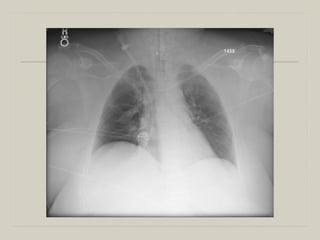

  70 WM with Stage 1 Sqamous Cell Cancer admitted to

ICU post-op after LUL resection – hypercapnic,

supported with BiPAP. On Day 3, he is worse:

WBC 25K

Temp 101.3

Intubated and bronched.

Not much secretions

PCT 3